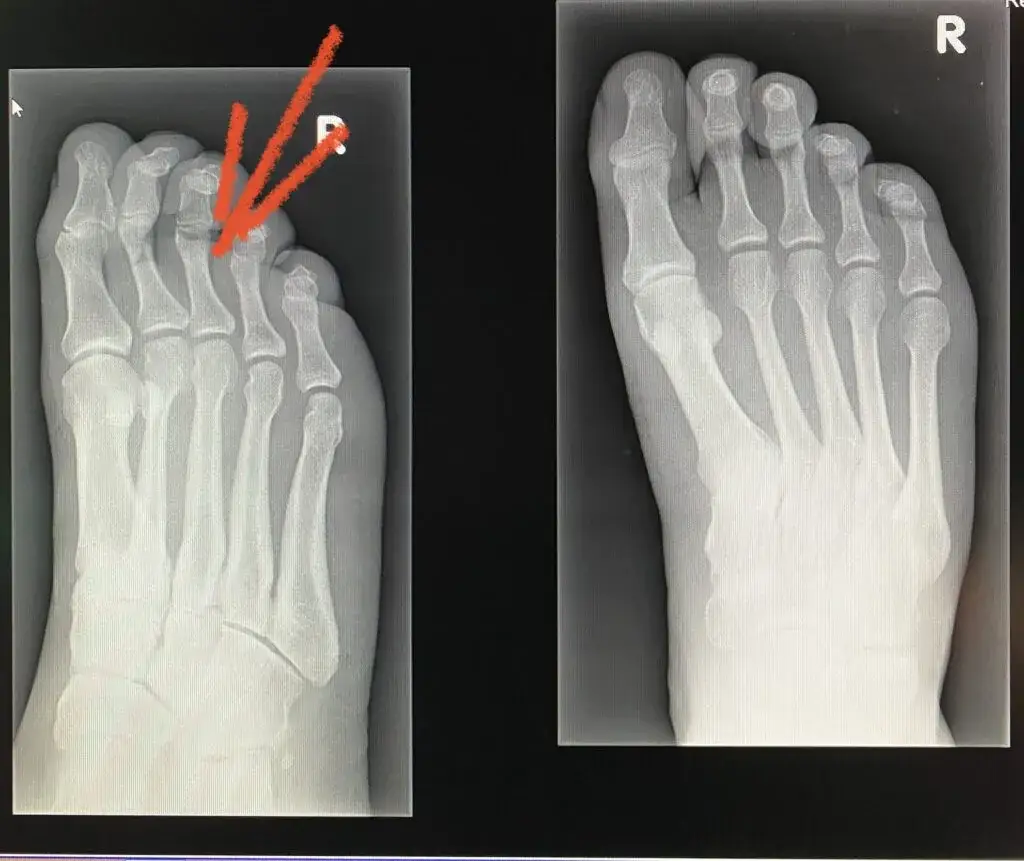

- RTG (rentgen): Służy głównie do oceny kości i stawów, pozwala wykryć złamania, zmiany zwyrodnieniowe, erozje kostne typowe dla RZS.